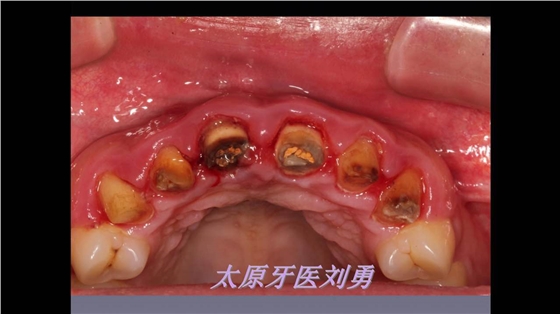

嚴重破壞生物學寬度,根尖瘺管,重行根管治療,第一次冠延長建立唇腭側及鄰面BW, 術后牙齦扇貝形差,齦乳頭黑三角,再次行美學冠延長,建立牙齦扇貝形,手術免費, 患者因經濟原因只能選擇鑄樁及鈷鉻合金烤瓷冠。終于完工